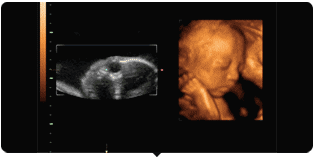

懷孕22周,就去醫(yī)院做大畸形篩查

通過(guò)四維彩超成像和我隔空見(jiàn)面

四維彩超就是四維成像技術(shù)(4D),能直觀、立體顯示人體器官的三維結(jié)構(gòu)及動(dòng)態(tài)、實(shí)時(shí)地觀察立體結(jié)構(gòu)。四維彩超可以檢查胎兒的發(fā)育情況,篩查先天疾病。如胎兒唇腭裂、四肢發(fā)育畸形、腦膜膨出、脊柱裂、腹壁裂等先天畸形。

四維彩超所使用的超聲檢查設(shè)備,有著出色的人體工程學(xué)設(shè)計(jì),是利用超聲波原理制作的一種儀器,不存在射線、光波和電磁波等方面的輻射,并且只是短時(shí)間的掃過(guò)人體,不會(huì)對(duì)寶媽和寶寶產(chǎn)生不良影響。